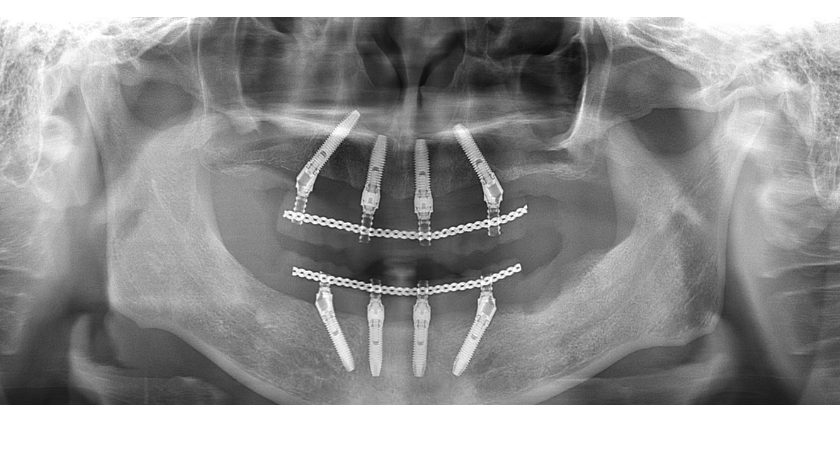

わずか4〜6本のインプラントを土台にして、上顎・下顎の歯列全体を一気に再建する治療法です。

1本ずつ入れれば10本以上必要なケースでも、4〜6本で支えられるように設計されています。

オールオン4は、骨の強い部位を選んでインプラントを配置します。

前歯部(骨が厚く比較的安定しやすい部位)に2本をまっすぐ埋入

奥の方(通常骨が薄くなりやすい部位)には後方に向けて傾斜角度をつけて2本埋入

この「傾斜埋入」によって、

広い支持範囲(後方延長)を確保しつつ、少ない本数で全体を固定できる構造が作られます。